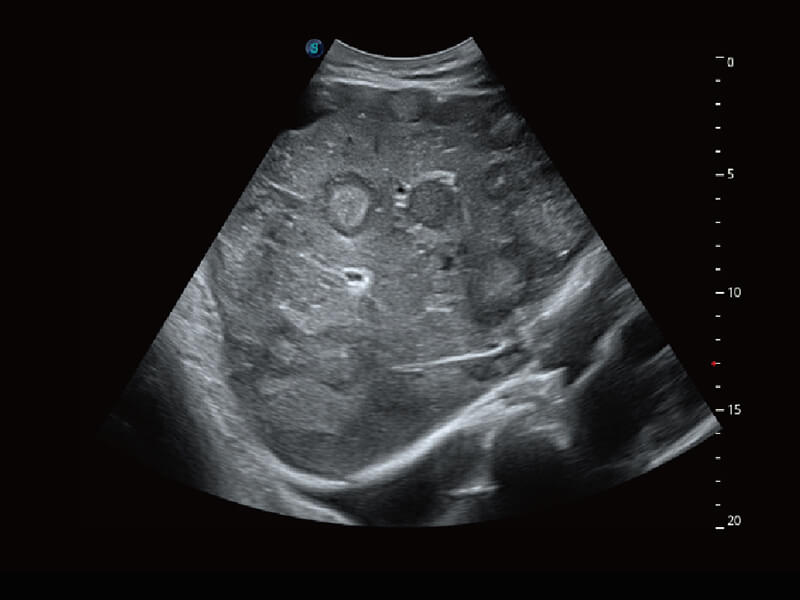

S60探头工艺,从前端信号处理每一个环节采集无损声学数据,真实还原组织原貌,再现解剖细节。